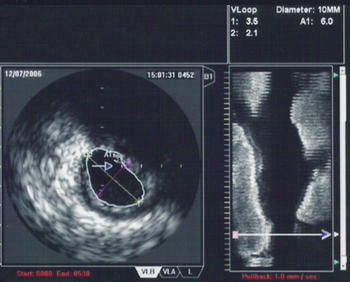

An IVUS image of the ostial left main coronary artery (left). The blue outline delineates the cross-sectional area of the lumen of the artery (A1 in the upper right corner), measuring 6.0 mm2. A two-dimensional mapping of the proximal LAD and left main coronary arteries is shown on the right.

One particular use of IVUS in the coronary anatomy is in the quantification of left main disease in cases where routine coronary angiography gives equivocal results. Many studies in the past have shown that significant left main disease can increase mortality,[11] and that intervention (either coronary artery bypass graft surgery or percutaneous coronary intervention) to reduce mortality is necessary when the left main stenosis is significant.

When using IVUS to determine whether an individual's left main disease is clinically significant, in terms of the desirability of physical intervention, the two most widely used parameters are the degree of stenosis and the minimal lumen area.[12] A cross sectional area of ≤7 mm² in a symptomatic individual[citation needed] or ≤6 mm² in an asymptomatic individual[13] is considered to be clinically significant and warrants intervention to improve one-year mortality. However, these exact cutoffs are up for debate and different cutoff cross-sectional areas may be used in practice depending on differing interpretations of the trial data.